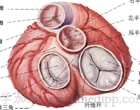

①瓣膜返流性疾病:如二尖瓣關閉不全,主動脈關閉不全,三尖瓣關閉不全等;

2、後負荷過度 主動脈瓣狹窄、三尖瓣關閉不全、厚性梗阻型心肌病胸厚型主動脈瓣下狹窄原發性高血壓、腎性高血壓、主動脈瓣狹窄肺動脈瓣狹窄、三尖瓣關閉不全、肥厚型梗阻性心肌病肥厚型主動脈瓣下狹窄、原發性高血壓、腎性高血壓主動脈縮窄、原發性肺動脈高血壓、Barnheim綜合徵妊娠毒血症、艾森曼格綜合徵。

3、前負荷過度 主動脈瓣關閉不全、二尖瓣關閉不全、乳頭肌功能失調房間隔缺損、動脈導管未閉、主一肺動脈隔缺損三腔心、急性腎小球腎炎、急性腎衰竭靜脈輸血、輸液過多過快、輸入鈉鹽或豬鈉激素過多室間隔缺損、先天性動靜脈屢、貧血妊娠、慢性肺源性心臟病。

風濕性心瓣病表現為二尖瓣狹窄二尖瓣雙病變(狹窄合併關閉不全),或雙瓣膜病變[二尖瓣與主動脈瓣狹窄和(或)關閉不全]。可根據雜音特點等作出心瓣受損的診斷但在心衰時,二尖瓣狹窄或主動脈瓣關閉不全的舒張期雜音可被肺淤血的呼吸音或肺部竣音所覆蓋引動房顫動或心室率加速影響心室肌充盈,也可使雜音減輕或消失給診斷帶來困難,直至心衰控制後雜音才易於聽清。擴張型心肌病和貧血性心臟病亦可因心腔擴大形成二尖瓣相對性關閉不全可在心尖區出現2/6-3/6級收縮期雜音或伴有舒張期雜音,與器質性二尖瓣關閉不全的鑑別是在心衰或貧血控制後減輕或消失。超聲心動圖對診斷有無器質性二尖瓣狹窄主動脈瓣狹窄有獨特價值。